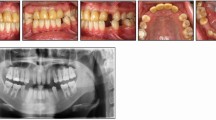

In this article statements related to the design of clasps are listed and discussed. The opinion of prosthodontic experts regarding these statements is indicated in the accompanying pie charts.

Davenport, J., Basker, R., Heath, J. et al. Clasp design. Br Dent J 190, 71–81 (2001). https://doi.org/10.1038/sj.bdj.4800887